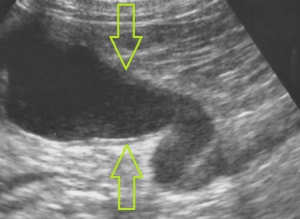

レントゲン検査により腎臓や尿管に結石が見つかった場合、さらに超音波検査によって結石の正確な位置関係とそれが周囲に及ぼす影響を評価します。下の2枚の写真は超音波検査の画像です。尿は左から右写真方向に「黒い管」として見える腎盂~尿管の中を流れます。

腎臓でつくられた尿がつまっているために尿管は重度に拡張しており、結石のすぐ上流で直径が4mm(赤矢印)、さらに腎臓の出口付近では1cm以上(緑矢印)にもなっており、腎臓内が拡張した水腎症になってしまっています。

通常では猫の尿管は極めて細いため超音波検査ではほぼ見ることができませんので閉塞の程度をイメージできるのではと思います。